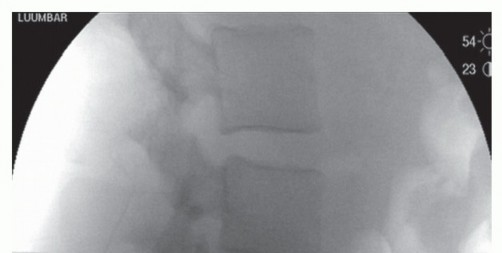

Slipped disc: Non-surgical treatment options Most people with a slipped disc in the lumbar region of their sp…